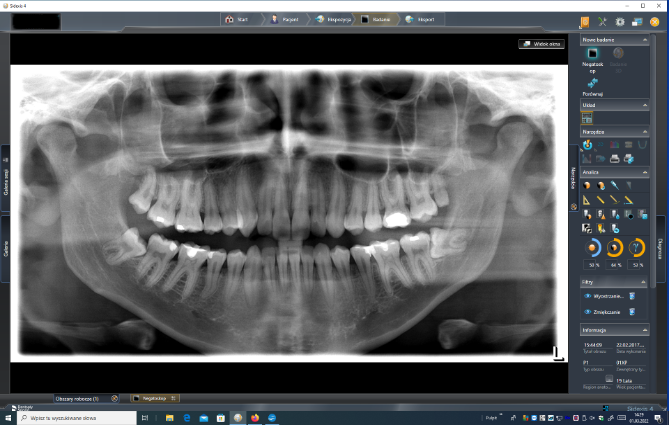

ZDJĘCIE PANTOMOGRAFICZNE- (pantomogram, panorama zębów) jest to jedno z podstawowych badań zlecanych przez lekarza stomatologa. Pozwala ono na jednoczasowe zobrazowanie struktur jamy ustnej: zębów, kości żuchwy, fragmentu kości szczęki, zatoki szczękowej, podniebienia twardego oraz stawów skroniowo-żuchwowych.

Główne wskazania: ocena ortodontyczna przed założeniem aparatu i do kontroli postępów leczenia, ocena zmian takich jak torbiele, nowotwory, nieprawidłowości rozwojowe, złamania wszystkich części żuchwy oprócz okolicy przednich zębów, choroby przyzębia, ocena obecności zębów zatrzymanych głównie mądrości, ocena wszelkich chorób przed założeniem protez całkowitych lub częściowych, ocena wysokości pionowej kości zębodołu przed założeniem imoplantów, ocena powierzchni stawowych głów żuchwy w zaburzeniach SSŻ , szczególnie u pacjentów którzy nie mogą otworzyć ust.